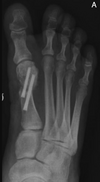

# Hálux valgo - No tratamento cirúrgico, o que consiste a **Osteotomia percutânea de Chevron**?

- Técnica relativamente nova e pouco citada nas bibliografias atuais para a prova do TEOT - Tem surgidos vários estudos à respeito. Para a prova, pode-se citar as características gerais da técnicas abertas na mesma topografia

45

# Hálux valgo - No tratamento cirúrgico, o que consiste a **osteotomia percutânea de Bosch**?

- Técnica relativamente nova e pouco citada nas bibliografias atuais para a prova do TEOT - Um fio K é mantido para manter a redução e depois da consolidação é retirado - Tem surgidos vários estudos à respeito. Para a prova, pode-se citar as características gerais da técnicas abertas na mesma topografia